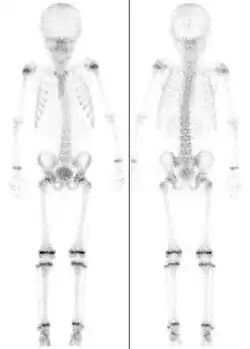

Für die Beurteilung auf Röntgenaufnahmen der am Handskelett des Menschen darstellbaren Epiphysenfugen gibt es spezielle Atlanten, die das chronologische Alter eines Kindes mit dem aktuellen Skelettalter vergleichen lassen (Abb.) Aufgrund der Vielzahl von Wachstumsfugen an den Handknochen, die sich alle zu unterschiedlichen Zeitpunkten knöchern verschließen, ist hier eine Zuordnung in Halbjahresschritten möglich.[4] Damit können, zusammen mit aktuellen Längenmessungen von Körpergröße, Sitzgröße, Beinlänge etc., Aussagen über das noch zu erwartende Gesamtwachstum des Kindes oder des Jugendlichen gemacht werden. Aufgrund der unterschiedlichen Geschlechtsentwicklung bei Mädchen und Jungen ist der Reifungsprozess und damit das Skelettwachstum bei Mädchen früher abgeschlossen. Die ersten Epiphysenfugen schließen sich bei Mädchen um das 14. Lebensjahr, die letzten Fugen beim Jungen nach dem neunzehnten Lebensjahr.